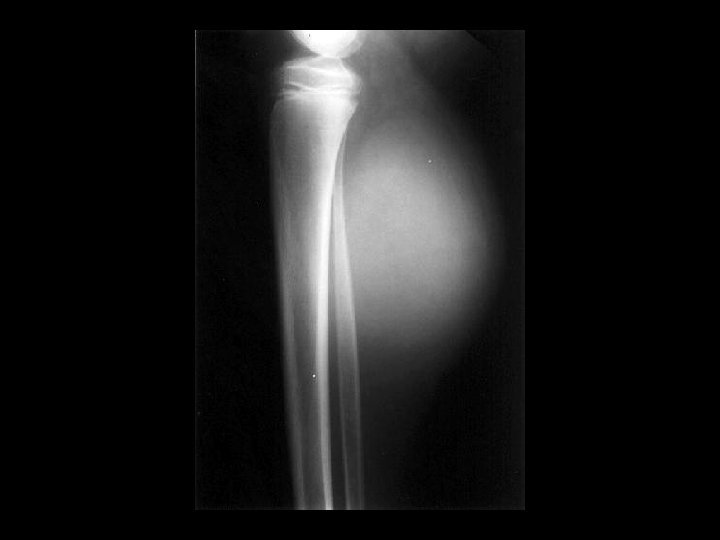

Aneurysmal bone cyst • Findings: – Lucent end of bone lesion in the proximal tibia – Slightly expansile, mild periosteal reaction – Fluid-fluid level on MRI • ddx: – Giant cell tumor – Unicameral bone cyst – Fibrous dysplasia – Chondroblastoma (rare)